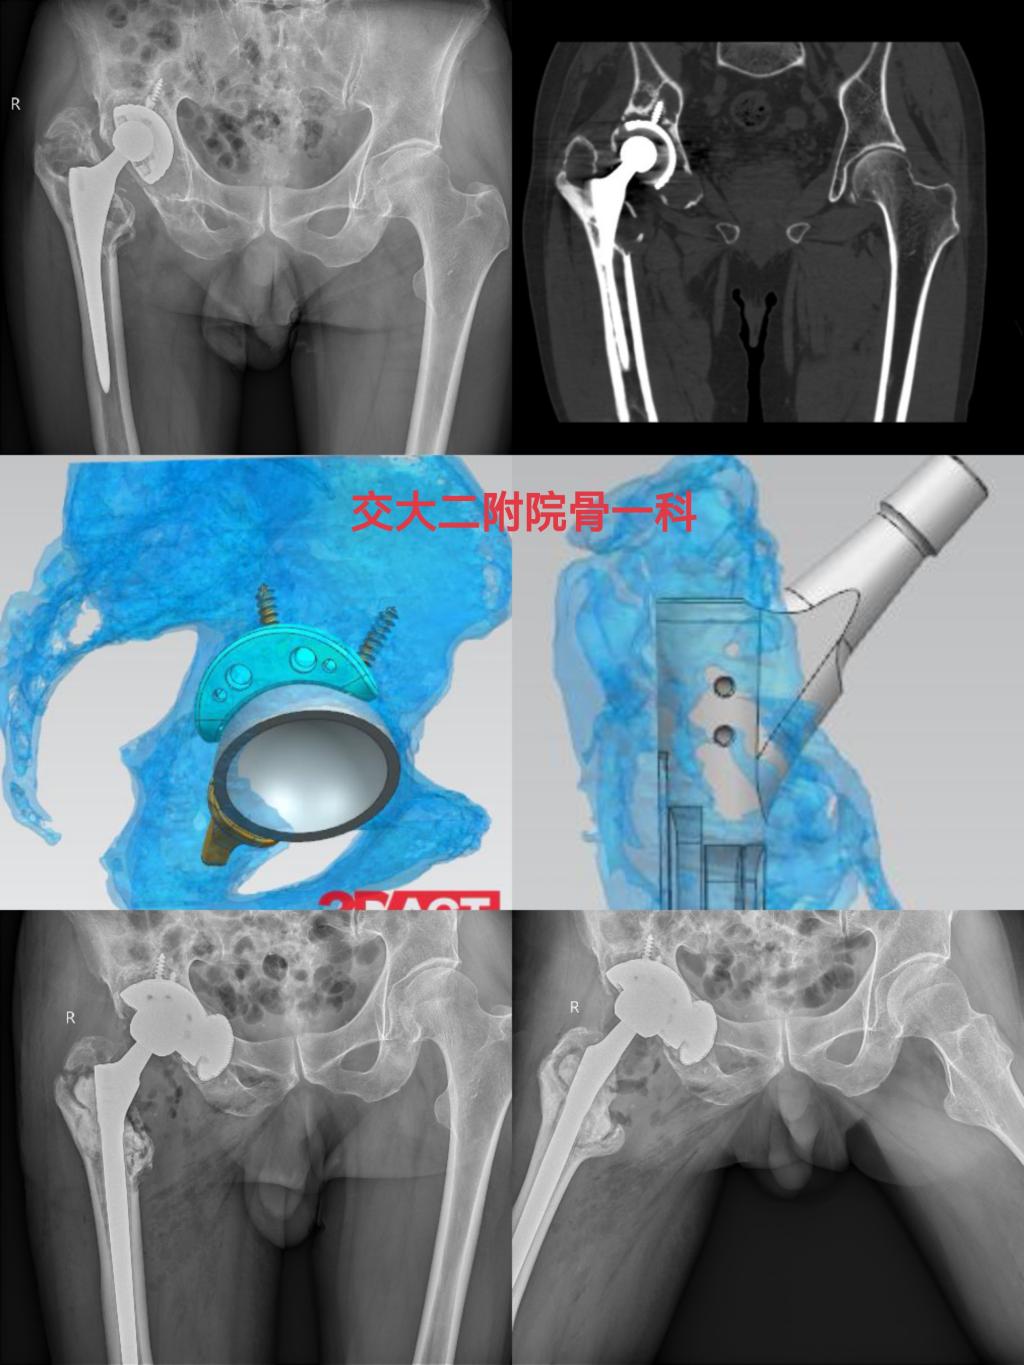

近期,骨一科收治多例需要进行髋关节复杂初次置换和翻修的患者,且病情复杂,手术难度大,党晓谦主任和时志斌副主任高度重视,组织全科对患者病情进行讨论分析,借助3D打印技术和计算机模拟手术技术,最终确定手术方案,在党晓谦主任的主刀下,手术顺利完成,术后患者恢复良好,均已顺利出院康复。

近期,一位左髋关节置换术后10余年、疼痛伴跛行2年的老年患者求助于骨一科,入院诊断为左髋关节置换术后假体松动,髋臼骨缺损(PaproskyⅢa型),股骨骨缺损(Paprosky Ⅱ型),骨质疏松症,完善相关检查排除手术禁忌后,由党晓谦主任主刀完成左髋关节假体翻修手术,术后恢复良好,已顺利出院。